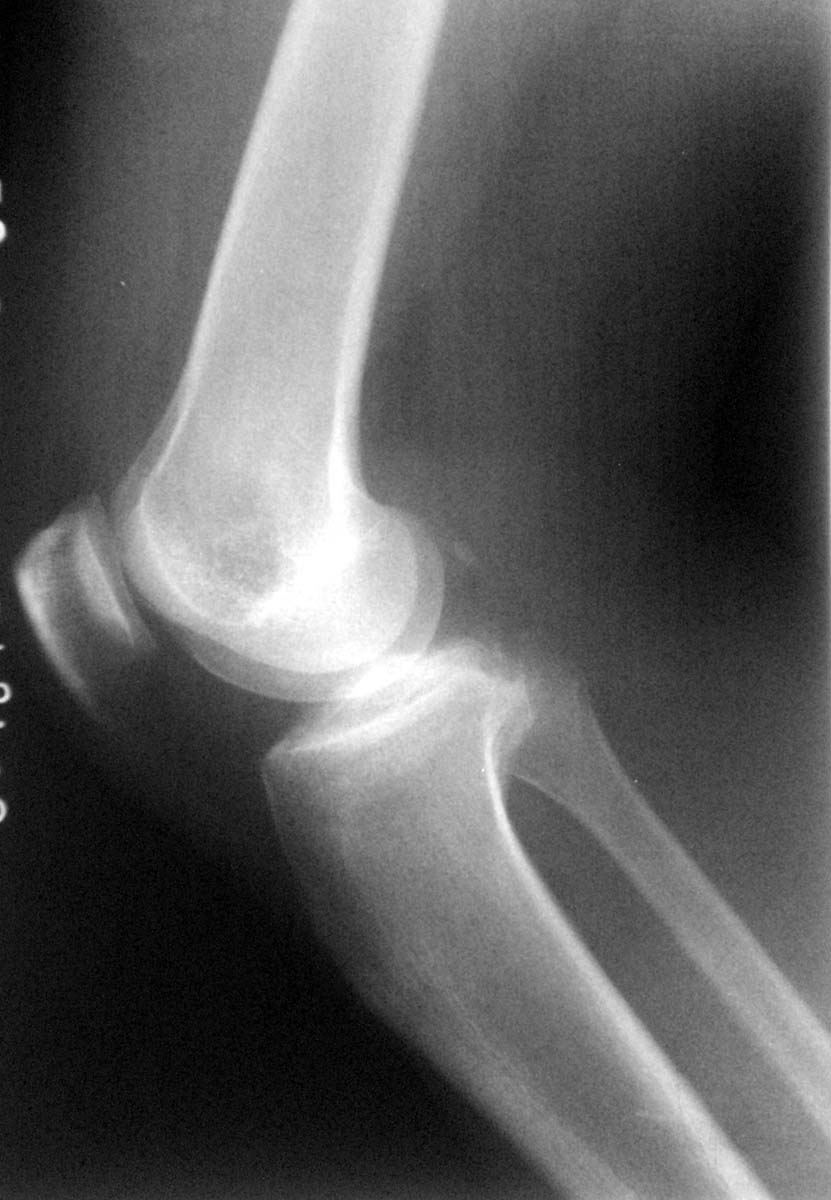

膝关节外伤,请看股骨内上髁外方是否为骨折?

支持楼主意见(撕脱性骨折)。

除了股骨外髁撕脱骨折外腓骨小头是否有骨折。

撕脱骨折。

应该是撕脱骨折。

撕脱骨折

支持撕脱骨折诊断,肌腱钙化不排除.

楼主说的外上髁,骨质未见明显异常;而内上髁有撕脱骨折.

股骨外上髁没发现异常,内上髁示斑片状骨质密度影,建议结合临床,透视旋转体位确定病人疼痛部位,撕裂骨折应该有固定疼痛。

支持撕脱骨折.高密度影内缘模糊,不象软组织的钙化,而且股骨内髁局部软组织肿胀明显.

不考虑骨折,因为结合正侧位片均未见主骨干上有与其等大之低密度区,所以本人考虑股内侧肌肌腱附着点钙化。

还是考虑撕脱性骨折为好,因为这个病人是因为外伤来的,并且与骨皮质不连续。

局限性骨化性肌炎>撕脱骨折,检查一下病人,局部的压痛是否明显

内上髁周围软组织肿胀,可考虑撕脱骨折,

不考虑骨折,因为我已发现两例,压痛点均不在此处,结合正侧位片均未见主骨干上有与其等大之低密度区,所以本人考虑股内侧肌肌腱附着点钙化。但愿能得到更好的证实!

不支持骨折。

支持钙化。

理由---1、边缘光滑锐利。2、相邻股骨无缺损。

为慎重起见1、检查此处有无压痛、外伤是否在此处。2、加照斜位。3、随诊复查。